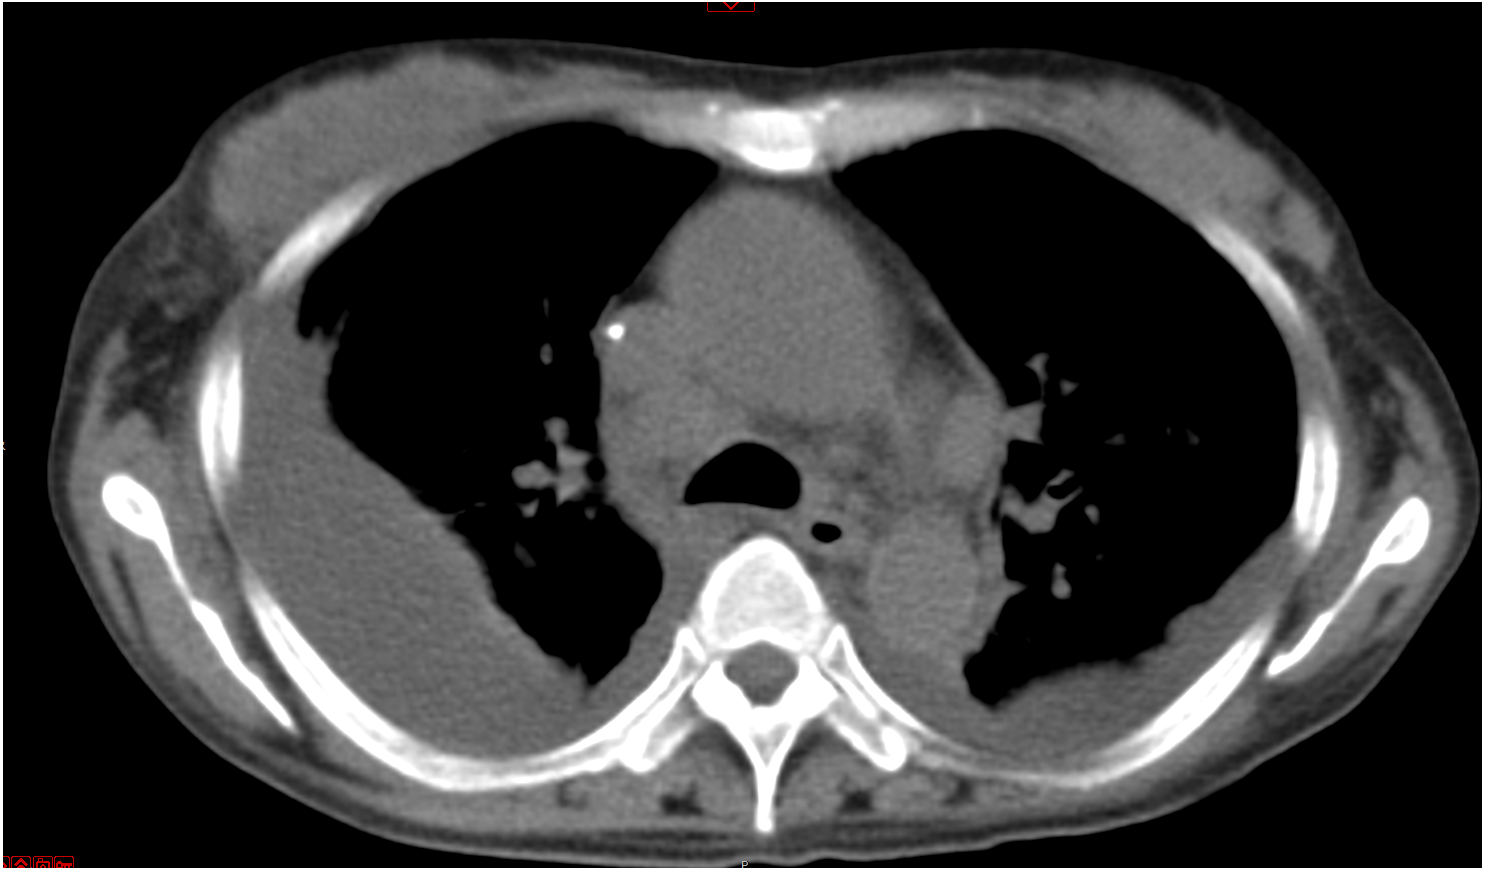

后再因“反复发热、多关节痛7月、皮疹3月”于2019-09-17入住本院风湿科。入院当天体温36.5℃,心率106次/min,呼吸20次/min,血压118/75 mmHg。步态正常,自主体位。左颈部肿大淋巴结。四肢和背部可见紫癜样皮疹,按压部分褪色,伴抓痕。腹软,肝脾未及。图 2为2019-09-21胸部CT结果,箭头所指为肿大淋巴结。

| 图 2 胸部CT示纵膈淋巴结改变 |